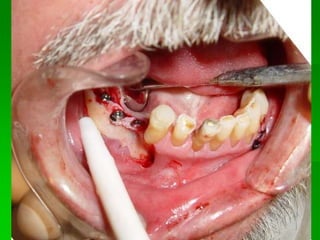

Implantes